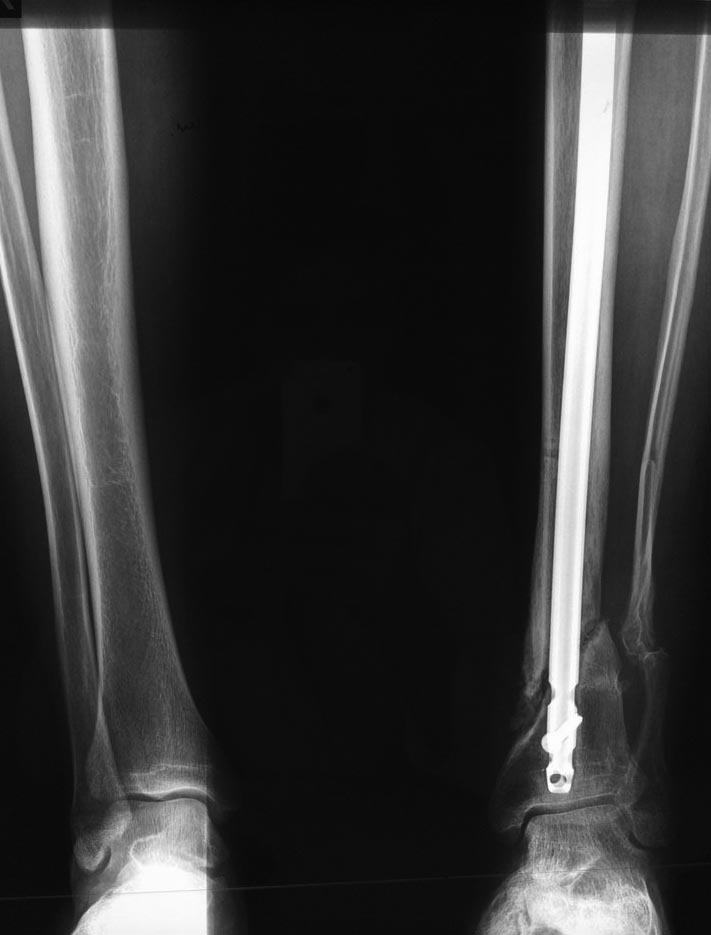

Через 6 мес. контроль - линия ложного сустава прослеживается, но имеется

периостальная костная мозоль.

Не хватает стабильности.

Вопрос что делать?

Вариант 1- выполнить реостеосинтез с рассверливанием КМК и на 12 мм

диаметра гвоздь (стоит 11 мм)и убрать ротацию стопы руками одномоментно

или одномоментно при помощи АНФ во время операции.

Вариант 2 выполнить удаление гвоздя, сделать все то же, что 6 месяцев

назад, но с восстановлением анатомических взаимоотношений в

голеностопном суставе.

Вариант 3 Двухэтапно, вторым этапом пластина на большеберцовую кость +

костная пластика области несращения.

Вариант 4 удаление гвоздя и лечение в КДА.